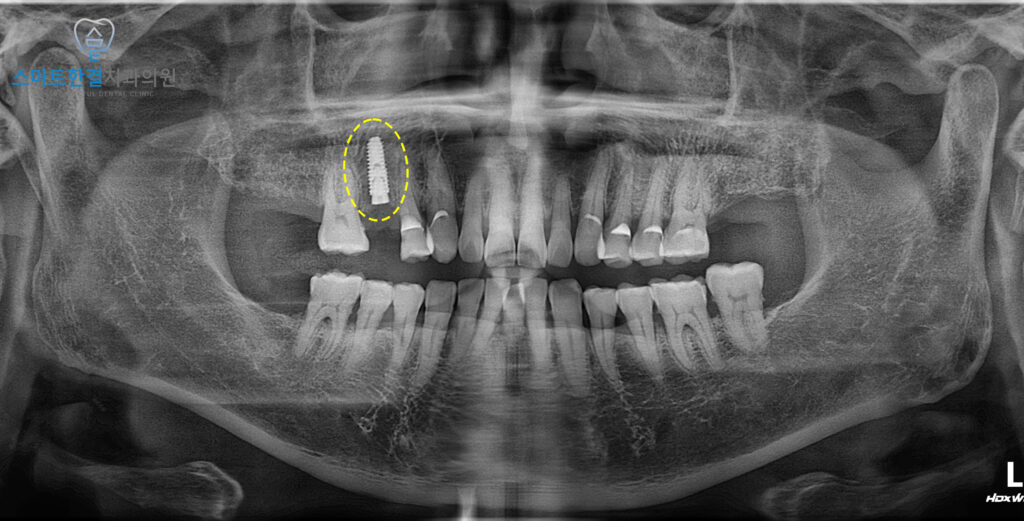

자세한 확인을 위해

엑스레이를 촬영해 보았어요.

일반적으로 미세한 파절이나 금은

엑스레이에서 잘 보이지 않는 경우가 많지만,

이번 환자분처럼 파절이 명확한 경우에는

뿌리까지 이어진 손상을 비교적

쉽게 확인할 수 있는데요.

실제 촬영 결과에서도

해당 치아의 파절선이 뚜렷하게 나타나,

치아 내부 구조까지 손상이

깊게 진행된 상태임을

확인할 수 있었어요.